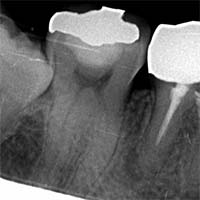

MTA / バイオセラミックによる3次元根尖封鎖

根の先端に行う“根尖封鎖”は、治療の成否を左右する超重要工程です。

![]() |

| MTA充填前 | MTA充填後 |

MTA・バイオセラミックは、

- 封鎖性が高い

- 硬化後の安定性が良い

- 骨の治癒を促す

- 組織親和性が高い

- 再感染が起きにくい

という特徴があり、現代の根管治療のゴールドスタンダードといえます。

Torabinejad(1995)もMTAは従来材料より漏洩が極めて少ないと報告しています: